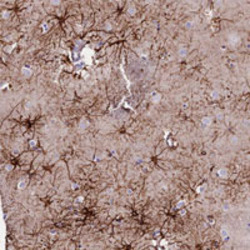

- Main image

- Experimental details

- Immunohistochemical staining of human lateral ventricle wall with VPS13C polyclonal antibody (Cat # PAB28112) shows strong cytoplasmic positivity in astrocytes at 1:200-1:500 dilution.

- Validation comment

- Immunohistochemistry (Formalin/PFA-fixed paraffin-embedded sections)